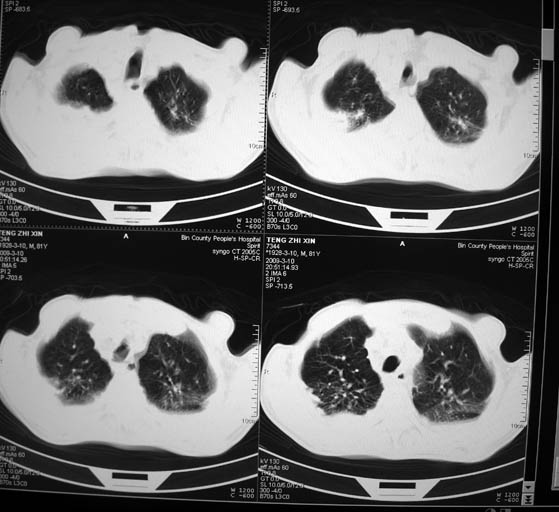

标题: CT18642:男,81岁,发热待查。

男,81岁,发热待查,右侧是占位还是膈疝?

右肺中央型肺癌并胸水。

右肺中央型肺癌并两侧胸水,左肺转移,腹水

1)考虑右肺下叶中央型肺癌并左肺转移。2)两肺上叶结核(陈旧性)。3)双侧胸腔积液。4)腹水。